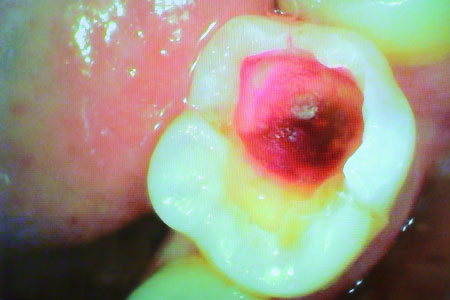

虫歯治療例 少し虫歯をとると大きな虫歯を発見

虫歯治療例 大きな虫歯